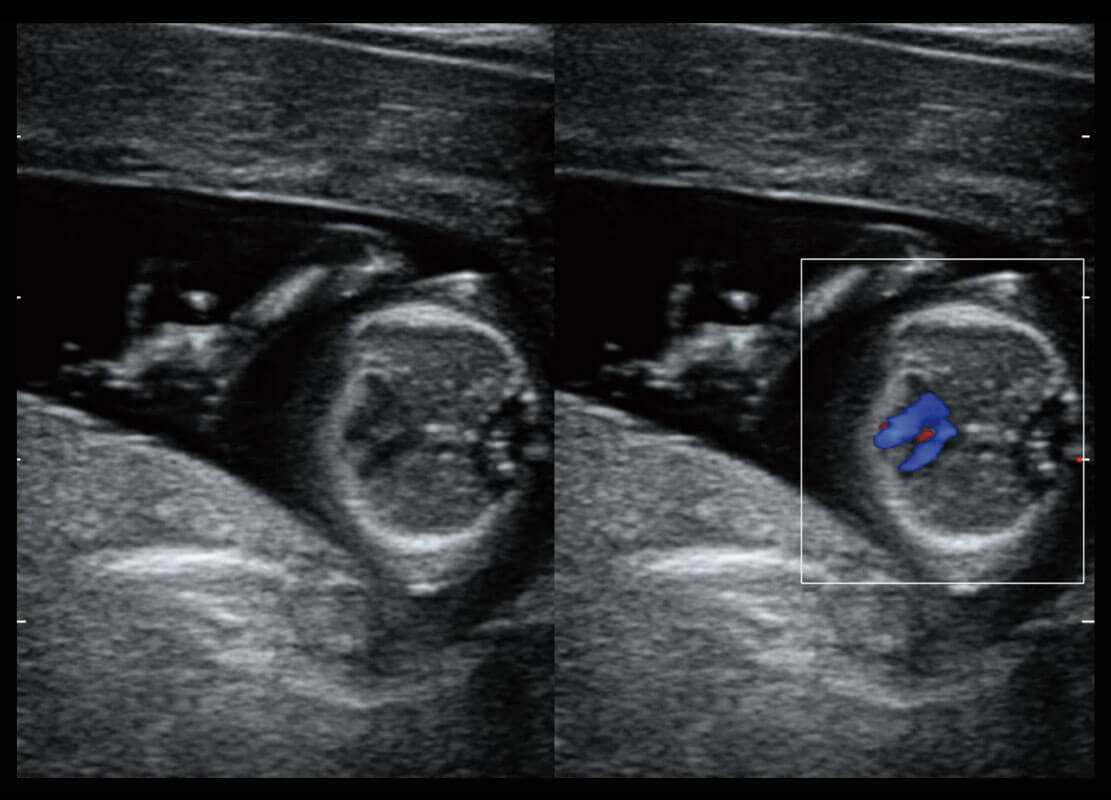

腔内妇科-卵巢

腔内三维-宫内节育器

腔内三维-光影成像